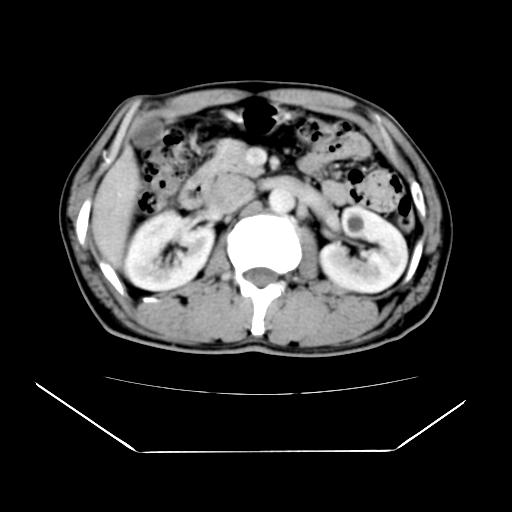

男性,55岁,外院体检afp明显升高,但b超未发现异常,否认乙肝病史。来我院ct增强。有延时扫描。

延时扫描完全充填,血管瘤

以下是引用yangyang2000在2009-5-23 20:17:00的发言:[br]延时扫描完全充填,血管瘤

肝脏右叶动脉期可见低密度影,至延迟期被充填,考虑血管瘤可能性大。

肝右叶病灶

不排除肝右叶肝癌可能。

如果这个是癌灶的话则下腔静脉有瘤栓可能

肝6段血管瘤

血管瘤可能性大。